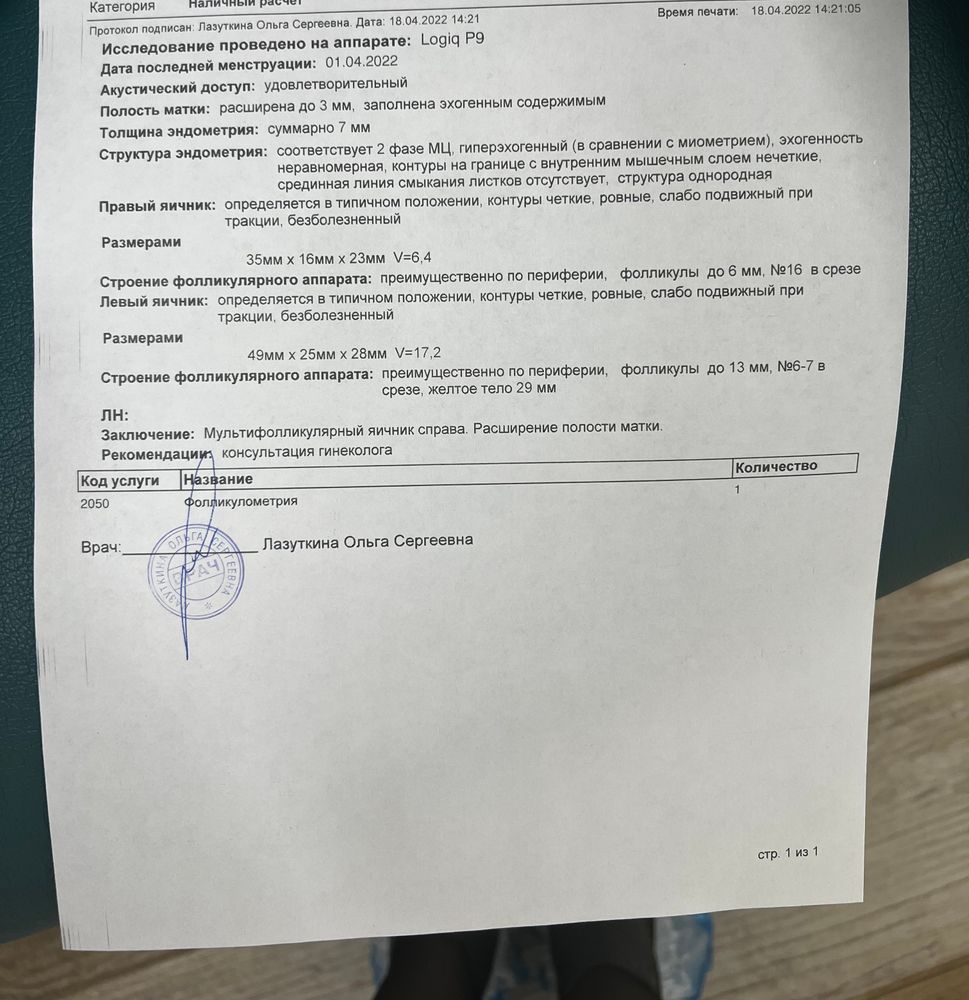

Сегодня зафиксировали по узи желтое тело 29 мм.

15.04 бал укол хгч 6000, до этого клостилбегит с 5 по 9 день.

Продолжаю на 14 дней дивигель и с сегодняшнего дня дюфастон.

Кстати, фото тестика на овуляцию 15.04 и сегодняшнее узи )))